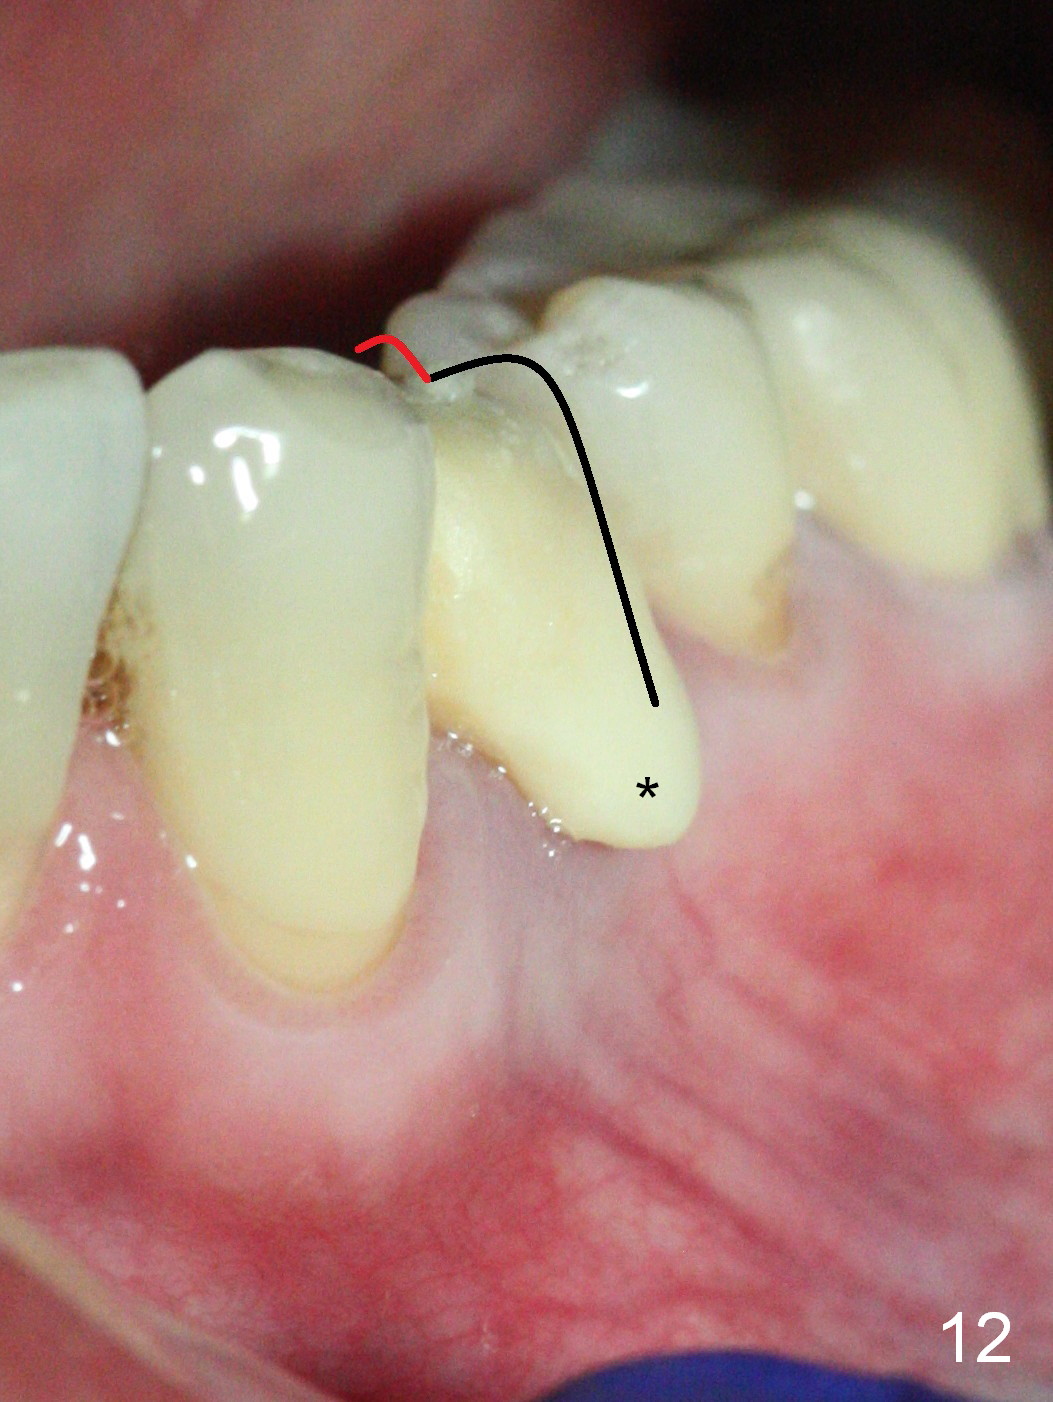

The implant seems to have osteointegrated 4 months postop (Fig.9). When a permanent crown is fabricated, it should have normal occlusal and buccal contour (from Fig.11 (provisional) to 12 red and black curved lines) as well as the buccal cervical extension (Fig.12 to cover the buccal gingiva (Fig.10 *). If the lingual margin of the abutment is too prominent, return the case and the abutment will be changed to the one with 2 mm cuff (existing 3 mm). The lingual margin of the abutment will be trimmed. The patient is not pleased with the short buccal margin of the crown after cementation (Fig.13). In fact the provisional should have been fabricated so that the its buccal margin should be subgingival and within the gingival outline. It may prevent buccal plate collapse. In fact the crown dislodges 1 year post cementation. The lingual margin is prep lower to increase the abutment height. Impression is taken. Although the access hole is unnecessary for cementation, it acts as an escape hole so that there is no excess cement cervically (Fig.14-18).